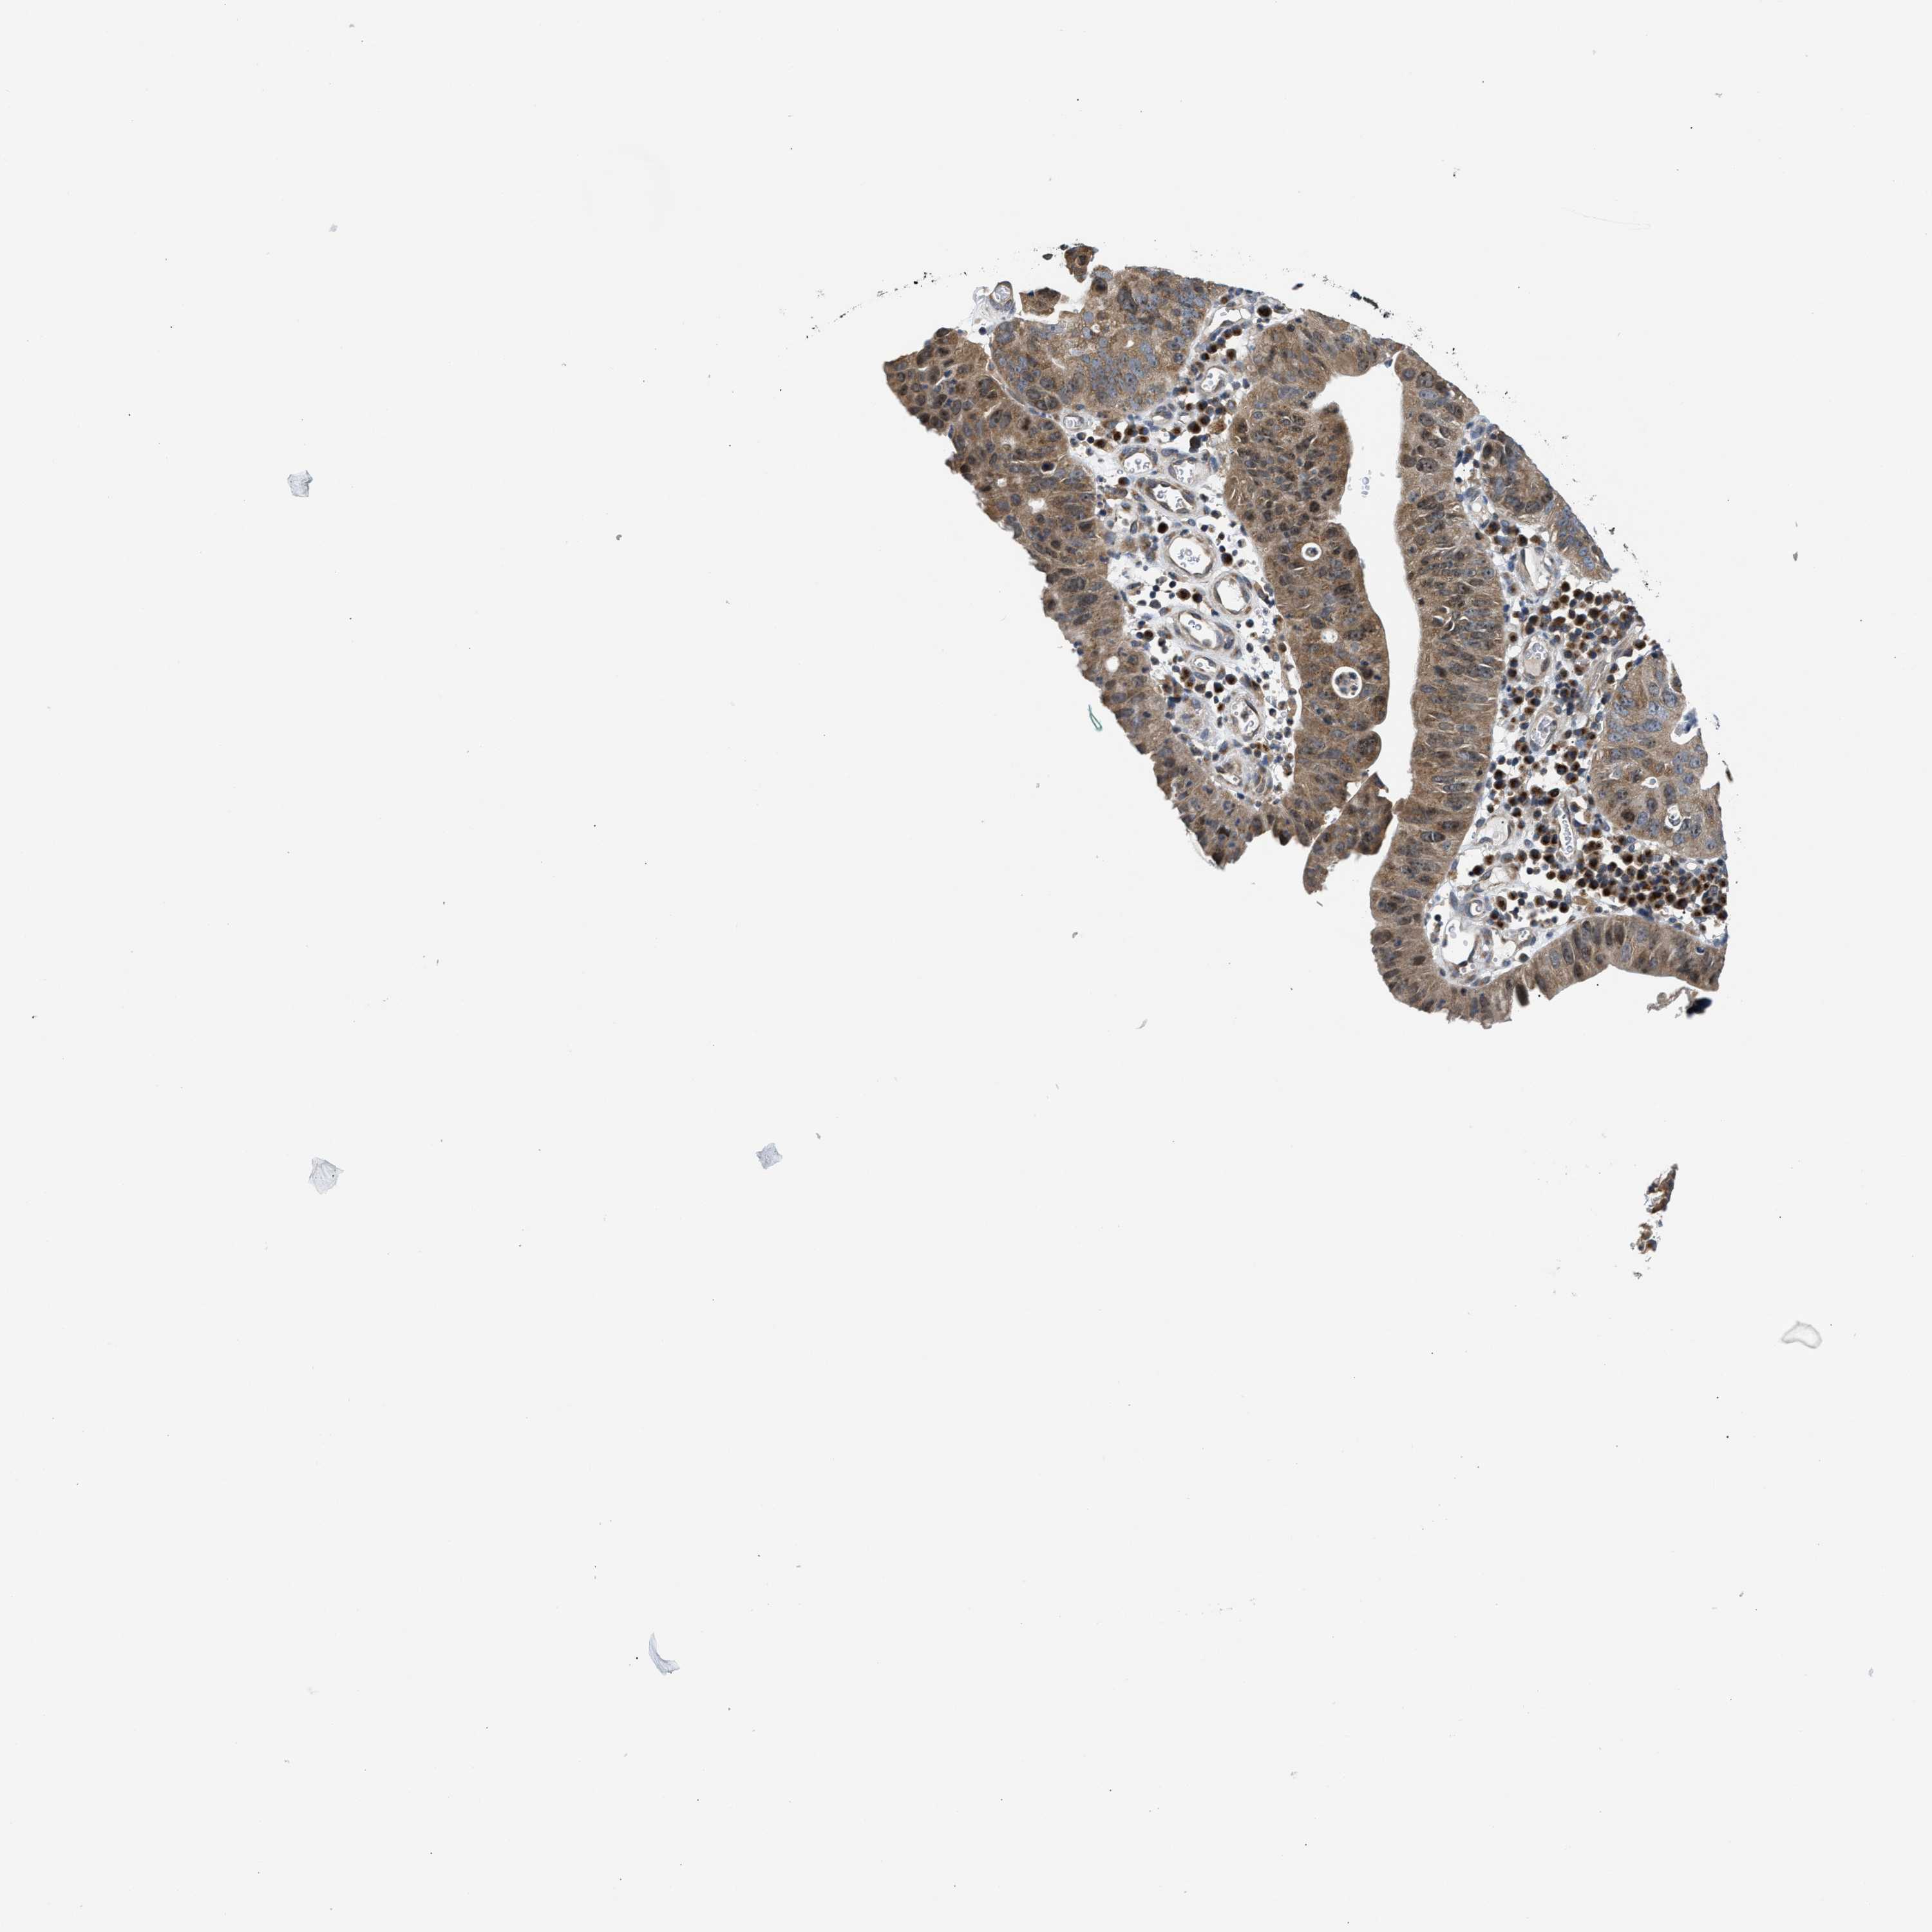

STOMACH CANCER - Protein expressioni

A mouse-over function shows sample information and annotation data. Click on an image to view it in a full screen mode. Samples can be filtered based on level of antibody staining by selecting one or several of the following categories: high, medium, low and not detected. The assay and annotation is described here.

Note that samples used for immunohistochemistry by the Human Protein Atlas do not correspond to samples in the TCGA dataset.

Antibody stainingi

Antibody staining in the annotated cell types in the current human tissue is reported as not detected, low, medium, or high, based on conventional immunohistochemistry profiling in selected tissues. This score is based on the combination of the staining intensity and fraction of stained cells.

Each image is clickable and will lead to virtual microscopy that enables deeper exploration of all samples and also displays staining intensity scores, fraction scores and subcellular localization as well as patient and tissue information for each sample.

Antibody HPA026303

Antibody CAB020822

Staining

High

Medium

Low

Not detected

Intensity

Strong

Moderate

Weak

Negative

Quantity

>75%

75%-25%

<25%

None

Location

Nuclear

Cytoplasmic/membranous

Cytoplasmic/membranous,nuclear

Adenocarcinoma, NOS

Adenocarcinoma, High grade